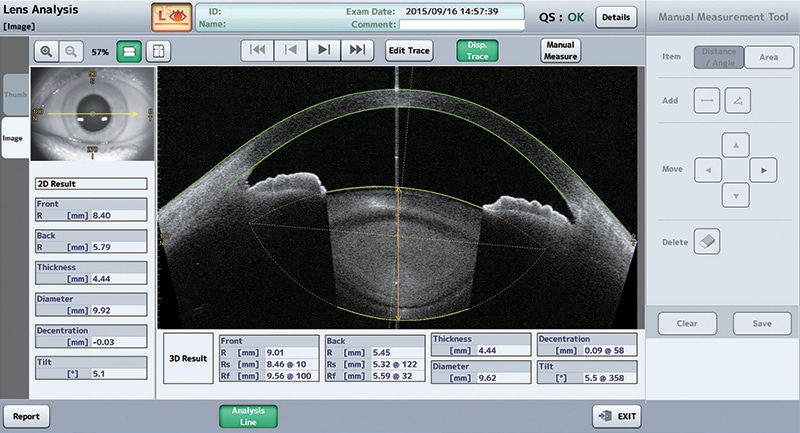

- Lens shape analysis & trend analysis

- Phakic IOL simulation